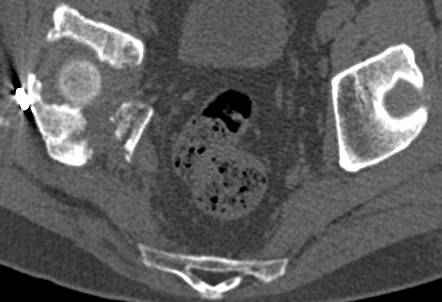

высылаю дополнительно сканы.

итак, второй вариант: высокий двухколонный с вовлечением КПС... Ни одно из основных повреждений не репонировано, кроме задней стенки. Скорее всего попытка реконструкции вертлуги сейчас будет очень травматичной и не очень эфективной, т.е. вероятный риск более значим, чем ожидаемая польза... Лучше подождать, и потом сразу эндопротез

подождать сколько, чего? такая дыра в задней колонне не закроется никогда.